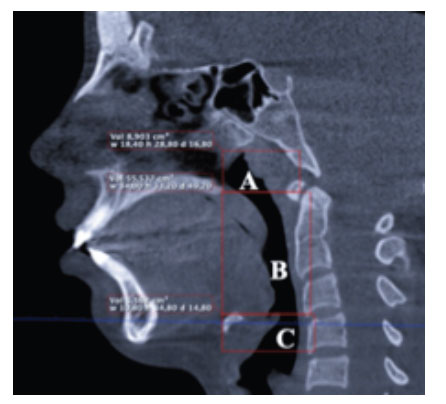

Los criterios de inclusión requerían que los pacientes sean de origen peruano ,dentición permanente y edad de 14 a 20 años. Los criterios de exclusión incluyeron pacientes con deformidades congénitas y adquiridas , antecedente de patología de vía aérea y antecedente de cirugía maxilofacial u ortodoncia. La muestra del estudio estuvo compuesta por 60 pacientes (20 TCHC clase I, 20 TCHC clase II, 20 TCHC clase III).Las TCHC fueron obtenidas de los archivos del equipo Planmeca Pro Max 3D Mid . El procedimiento de medición se realizó a través del software PLANMECA Romexis Viewer, a través del método de observación directa, en una pantalla de 21,5 pulgadas de la marca Apple iMac, donde se procedió a la ubicación de los limites anatómicos, según Guijarro-Martínez y Swennen 4.Donde la nasofaringe tiene su limite superior que va del contorno del tejido blando de la pared faríngea hasta su limite inferior en el plano paralelo a la Horizontal de Frankfort (HF) que pasa por la Espina Nasal Posterior (ENP) y se extiende a la pared posterior de la faringe. La orofaringe llega en su limite inferior al plano paralelo a HF que pasa por C3ai (punto mas anteroinferior del cuerpo de la tercera vertebra cervical) .La hipofaringe tiene su limite inferior en el plano paralelo a HF, conectando a la base de la Epiglotis o a la entrada del esófago (figura 1).

Se encontró el volumen en cm³ en cada patrón esquelético facial a través de la herramienta “región de crecimiento 3D” , en cada segmento de la vía aérea superior, los cuales fueron clasificados según el ángulo ANB (Clase I: 1° ≤ ANB ≤3°, clase II: ANB >3°, y clase III: ANB<1° 7 )previamente a través de una vista sagital cefalométrica (figura 2).